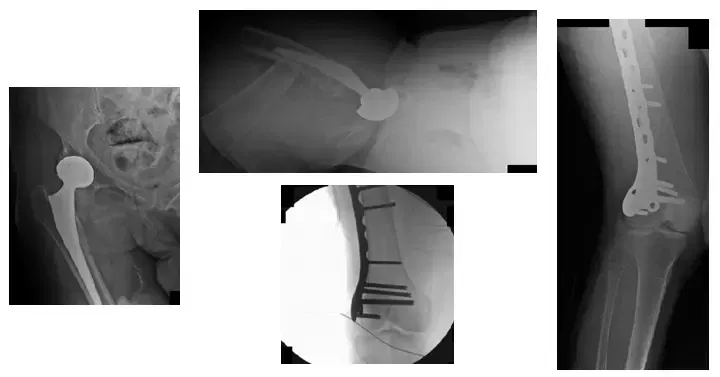

La paciente es una mujer de 65 años que acudió aproximadamente un año después de someterse a una artroplastia total de cadera derecha y presentaba una fractura de fémur desplazada. El paciente necesitó un procedimiento de fijación interna de reducción abierta (ORIF)...